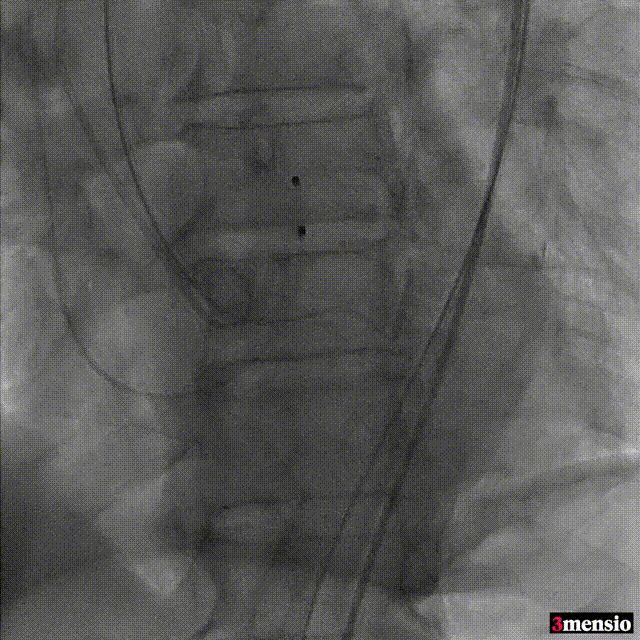

标准位释放定位

23mm球囊后扩

术后造影

瓣膜定位精准,标准位释放,轻微瓣周漏,术后效果良好,手术取得圆满成功。